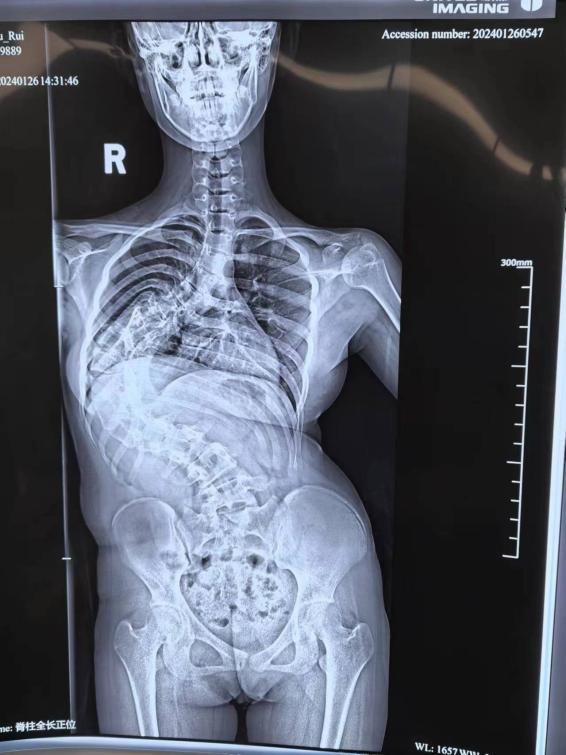

安徽花季少女脊柱侧弯达130度 手术矫治使其长高11厘米 7月24日,记者安徽省儿童医院(复旦儿科安徽医院)骨科了解到,来自安庆的16岁少女媞媞(化名)是一位重度脊椎侧弯患者,脊柱侧弯达130度,在近期进行了分期手术矫正。矫正后媞媞的身高增长了11厘米,目前已经顺利康复出院。